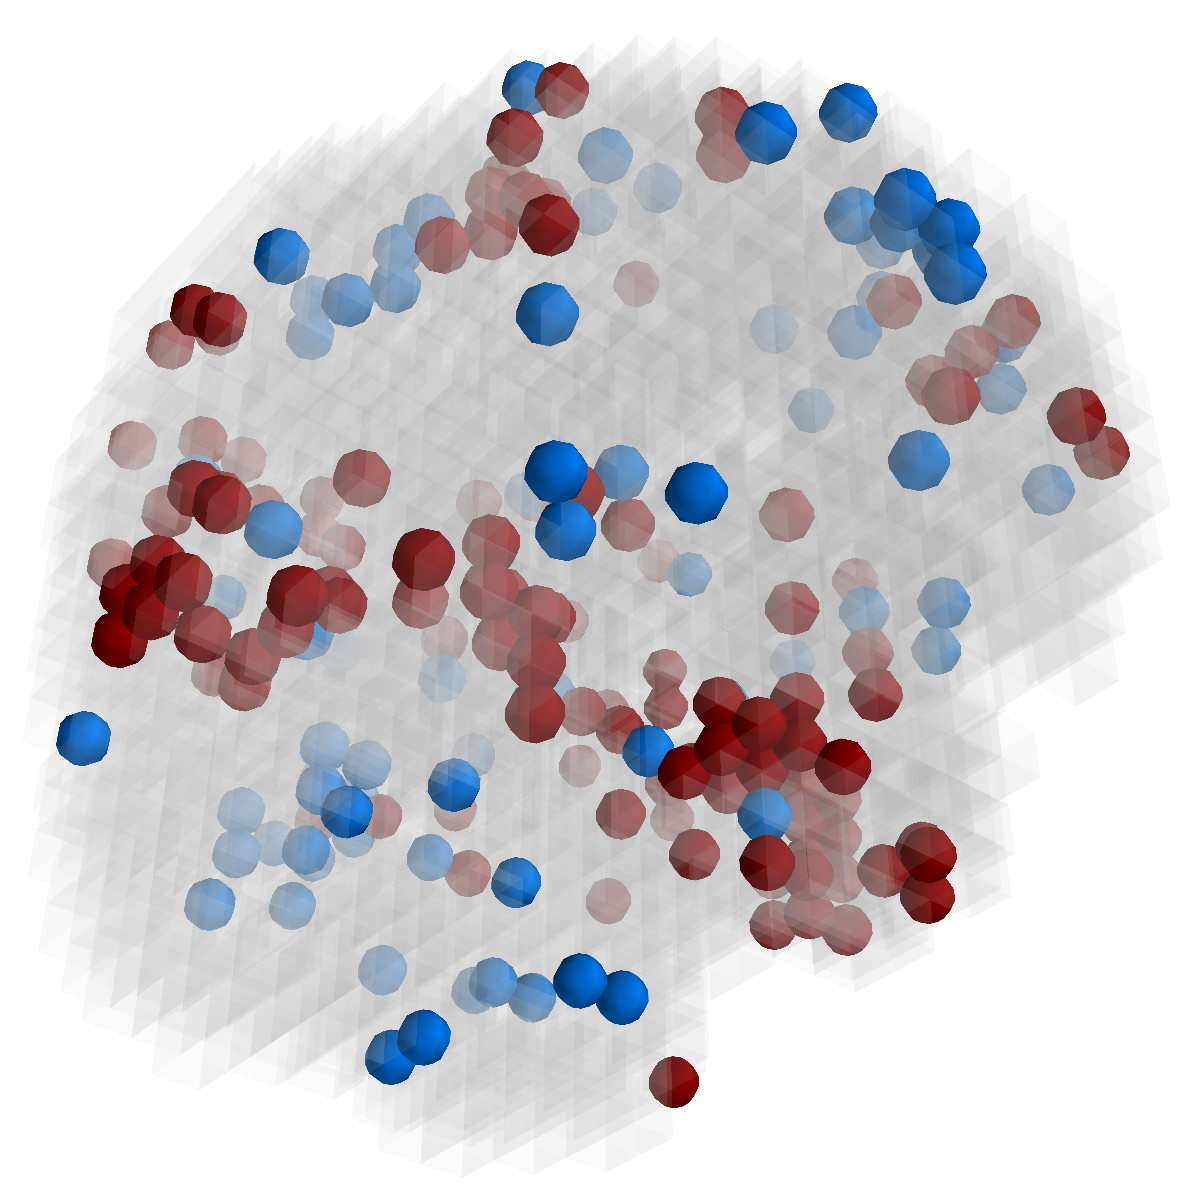

Figure 2: Feature selection by different models. The top row illustrates selected voxels in a 3D model (voxels with positive β𝛽\beta are in brown and negative ones are in blue), the mid and bottom rows illustrate the corresponding projections on brain slices.

Feature selection. For each task, the selected features are those whose β𝛽\beta are not zero . In Figure 2, the result of 30ADNC is used to illustrate the feature selection by different models (using the parameters at their best accuracy). As shown, the selected voxels by both GFL and n2superscript𝑛2n^{2}GFL cluster into several spatially connected regions, whereas those of lasso and T-test/MLDA scatter around. Also, as mentioned before, the LapL tends to select much more voxels than necessary due to the l2subscript𝑙2l_{2} regularization. Moreover, the selected voxels by GFL and n2superscript𝑛2n^{2}GFL are concentrated in Hippocampus, ParaHippocampal gyrus (which are believed to be the early damaged regions). On the other hand, the lasso and T-test/MLDA either select less lesion voxels or select probably noisy voxels not in the early damaged regions.